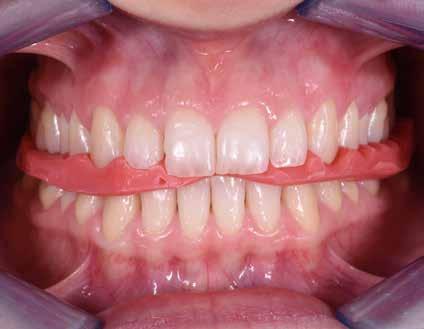

Fig. 118 > Apparecchio elastodontico all’interno del cavo orale: è possibile

apprezzare il grande lavoro che lo stesso svolge sulle strutture scheletriche, sui muscoli delle labbra e della lingua; di qui l’effetto tridimensionale della terapia elastodontica.